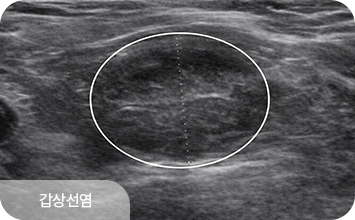

겉으로 드러나지 않는 호르몬 이상이나 결절을 조기에 발견해

갑상선 질환을 초기 단계에서 정밀하게 진단합니다.

결절이 발견된 경우에는 초음파 소견을 바탕으로 판독 후,

필요에 따라 세침흡인검사 또는 총조직검사를 시행합니다.

갑상선 질환은 결절의 크기보다,

구조적 특성과 변화 양상을 함께 살펴야 합니다.